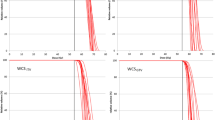

Figure 2 shows representative dose distributions for the 3-phase SFUD and IMPT plans. It shows the dose distribution for CT40%, CT50%, CT60%, and 4DDD. In the modeling of 4DDD calculation algorithm, the MU of a spot delivered at a given time is divided into adjacent-phase CTs with weighted factors considering the remaining breathing times of each phase. Due to the specification, the dose at the center phase CT (CT50%) tended to increase than the other phases. In contrast, the dose at the CT60% (the end of gating) decreased because the delivery spots may be less than the other phases owing to the combination of the synchrotron operation pattern and the breathing motion pattern. Figure 3 shows a comparison between SD and 4DDD for the 5-phase plans.

The upper panel of Table 2 lists the mean values and standard deviations of the DVH indices for the SD and 4DDD for the 3-phase SFUD and IMPT plans. The p values show the results of the statistical tests for the SD and 4DDD plans. In both techniques, 4DDD had significantly lower D95%, D98%, and V100% and higher HI than SD. In contrast, 4DDD had a higher CN in SFUD and a lower V98% in IMPT than in SD. The lower panel in Table 2 lists the mean values and standard deviations of the DVH indices for SD and 4DDD and the p values for the 5-phase SFUD and IMPT plans. In both techniques, 4DDD had significantly lower D95%, D98%, V98%, and V100% and higher D2% and HI than SD. In addition, 4DDD had higher CN content in SFUD than in SD. For the OARs in both SFUD and IMPT, there was a statistically significant difference only between SD and 4DDD in esophageal Dmean.

Evaluation of plan robustness against interplay effect

Table 3 lists the differences in the DVH indices (ΔI) for the 3- and 5-phase SFUD and IMPT plans. The p values show the results of the statistical tests for the SFUD and IMPT plans. In the 3-phase SFUD plans, the deterioration rates were significantly higher for V100%, HI, and CN, with smaller absolute deviations for V98% than for the IMPT plans. Significantly higher deterioration was observed for V100% and HI in the 5-phase SFUD than in the 5-phase IMPT. Notably, in both the 3- and 5-phase plans, there was no statistically significant difference in the deterioration rates of the OAR indices between SFUD and IMPT.